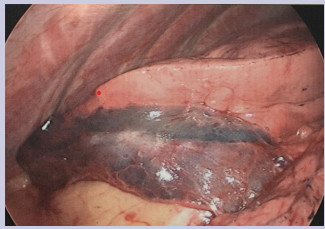

Fiberoptic bronchoscopy revealed streaks of blood in the left main bronchus. Fresh blood and blood clot was found in the inferior lingular segment of the left upper lobe. Broncho-alveolar lavage was performed in the left upper lobe inferior lingular segment and the return was bloody. Broncho-alveolar lavage specimens were sent for microbiology and cytology and were negative for infection and malignancy. Given the findings of active persistent bleed, 3-D and MIP reconstructions were done from the prior CT Chest which did not show any bronchial artery branches or parasitized intercostal artery branches supplying the lingular consolidation. There were only normal sized pulmonary arteries and veins supply the inferior segmental lingular consolidation. It was deemed by Interventional Radiology that the vessels are not amenable for embolization, given the lack of classic features of pulmonary arterio-venous malformation. Thoracic Surgery was consulted for resection of the lingula. Patient underwent video assisted thoracoscopic surgery and was found to have marked discoloration of the lingula [Figure 3] and wedge resection of the lingula was performed.

Figure 3: Gross specimen of the lingula